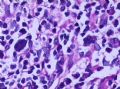

女,45岁,发现颈部多个淋巴结肿大,体查时发现全血细胞减少.取最大的淋巴结送检.

图2

淋巴结结构破坏,有明显异常细胞,结合病史,考虑恶性,淋巴瘤、白血病?不知血片分类怎样?待组化和专家讲解。谢谢!

恶性,考虑淋巴造血系统肿瘤。NHL或白血病。

恶性是肯定,就是要排除转移的恶黑。再考虑原发的非何杰金